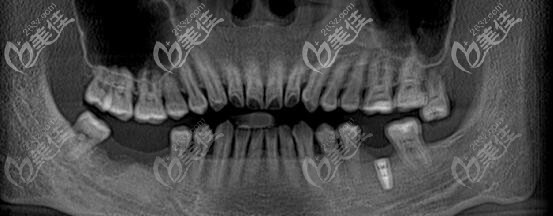

術(shù)前照片:

術(shù)后照片:

牙齒情況:左下后牙種植過一顆,右下后牙缺失兩顆;

治療方案:顧客咨詢后,要求植入諾貝爾種植體;